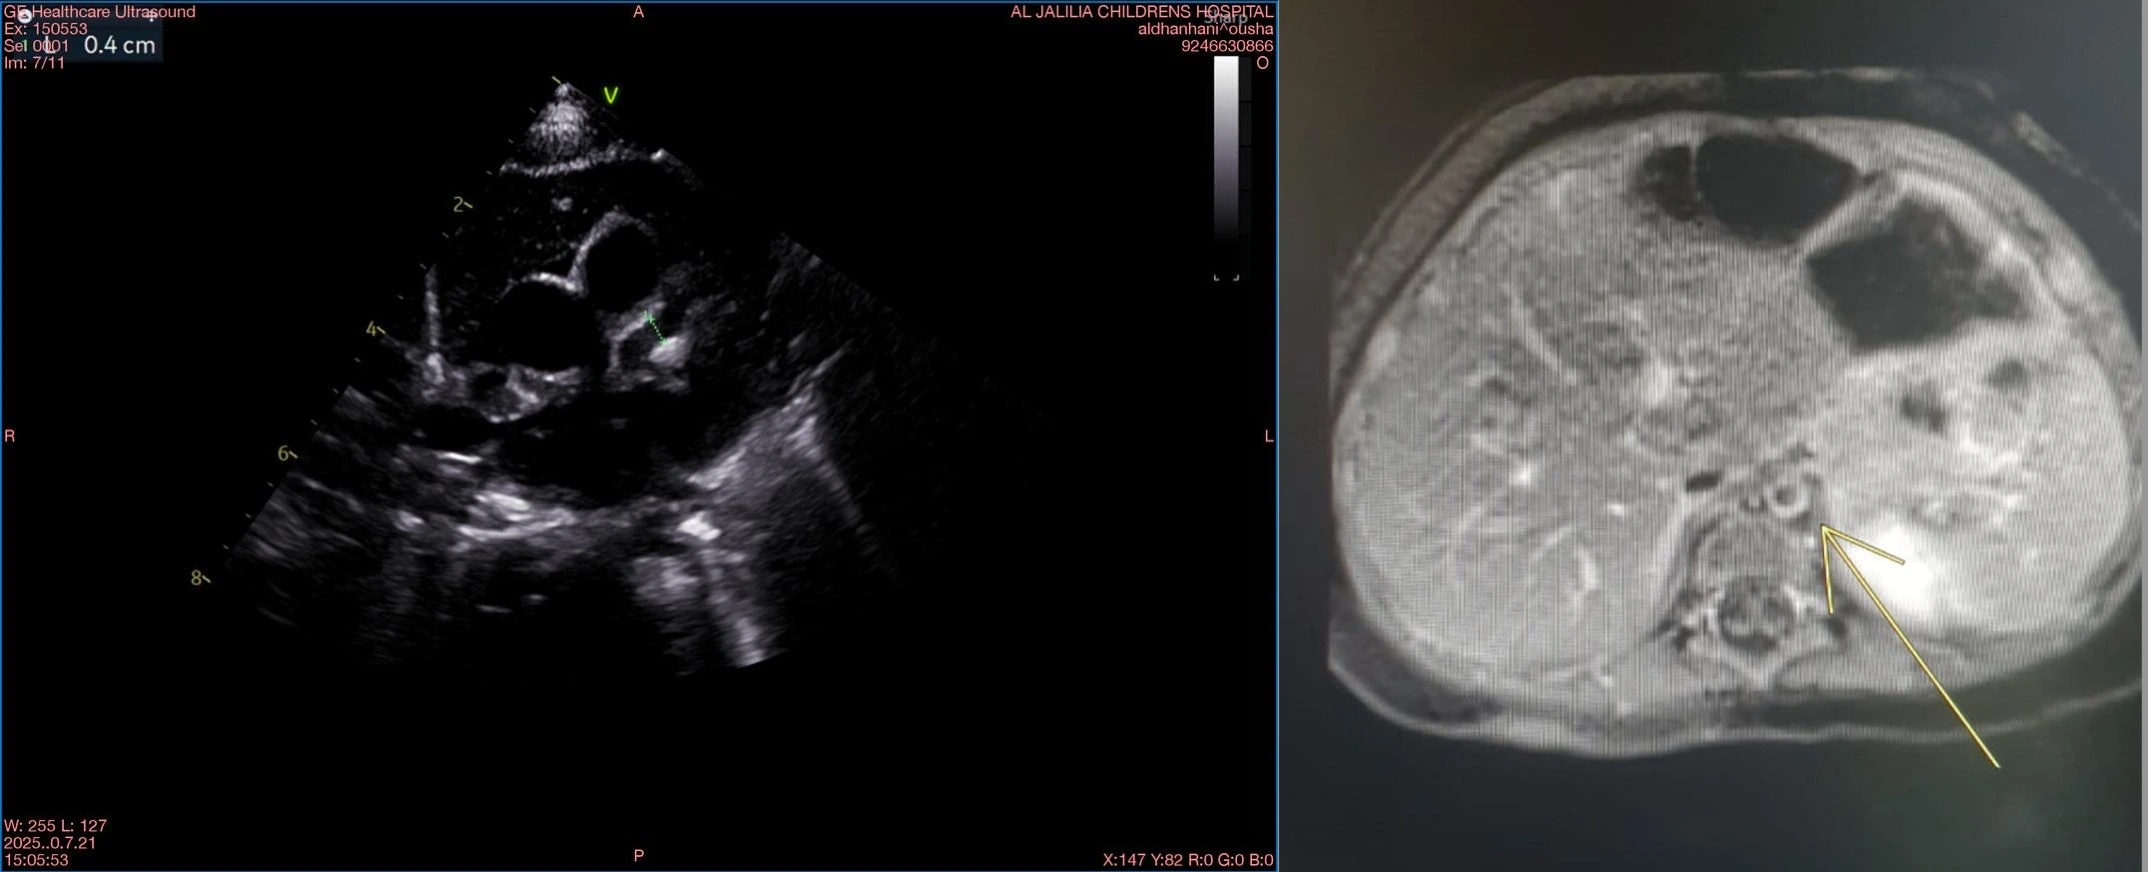

Case presentation: We report a 3-month-old term infant presenting with isolated high-grade fever lasting 9 days, with no classical KD clinical signs. Examination revealed a soft systolic murmur but was otherwise unremarkable. Laboratory evaluation showed normocytic anaemia, marked thrombocytosis (platelets 1,116 × 10^9/L), elevated C-reactive protein (50.4 mg/L), and raised inflammatory markers including fibrinogen, IL-6, D-dimer, and pro-BNP. A comprehensive infectious workup was negative. Given persistent fever beyond 10 days and elevated inflammatory indices, intravenous immunoglobulin (IVIG) (2 g/kg) and moderate-dose aspirin (30 mg/kg/day) were initiated early despite incomplete criteria. Echocardiography confirmed giant coronary aneurysms with left anterior descending artery 4 mm Z-score +12 (Figure 1(A)) and diffuse coronary dilation. Multidisciplinary management included corticosteroids, clopidogrel, and therapeutic enoxaparin guided by anti-Xa levels. Magnetic resonance angiography (MRA) revealed diffuse aortitis involving the descending thoracic and proximal abdominal aorta (Figure 1(B)) and vertebral artery inflammation, demonstrating systemic vasculitis beyond the coronaries. Genetic testing was also sent and is awaiting results. The patient improved clinically and biochemically, with regression of coronary dilatation on serial echocardiograms and normalized inflammatory markers on follow-up. Oral corticosteroids were tapered over three weeks under close cardiology and rheumatology supervision.